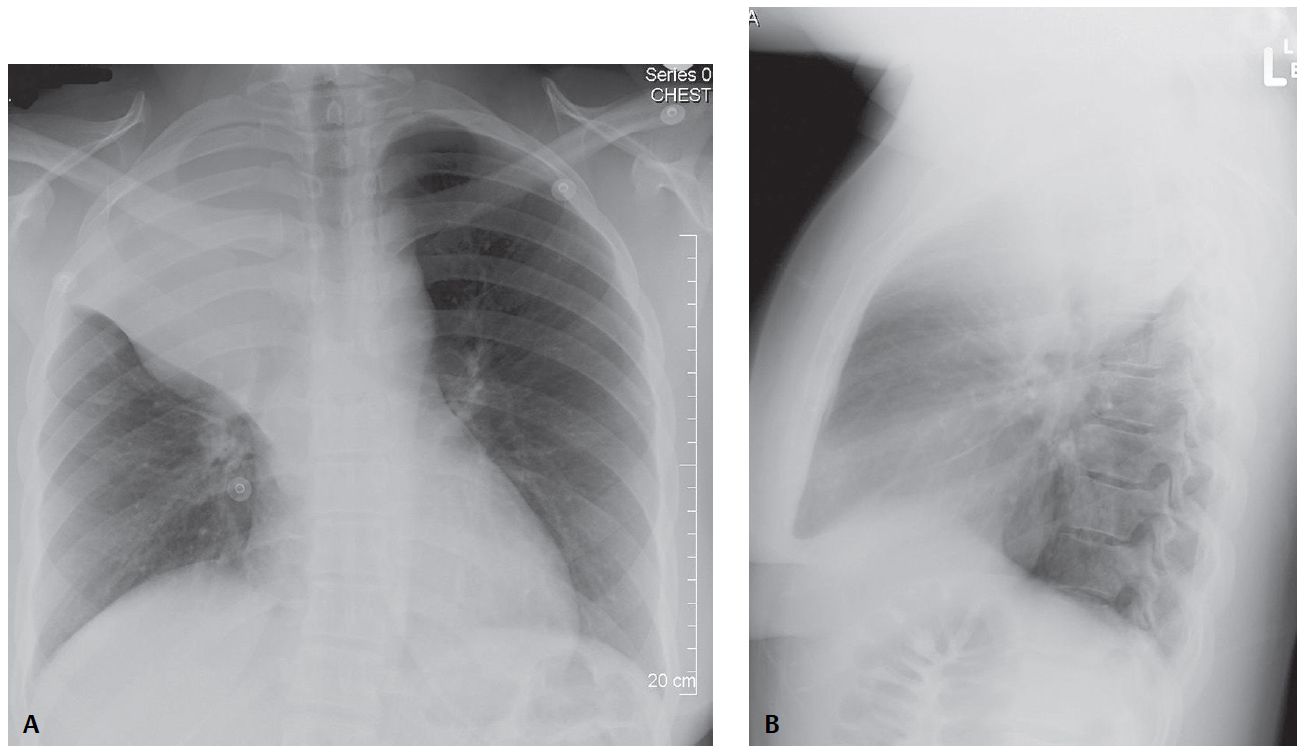

PA and lateral chest X-rays reveal reduction in volume of the right hemithorax, right hemidiaphragm elevation, and a “peaked” appearance (i.e., juxtaphrenic peak) of the superomedial hemidiaphragm. The trachea is minimally displaced to the right.

On the frontal exam, the horizontal fissure is displaced cephalad. A mass-like convex-appearing buge is present in the inferior and medial portion of the fissure. The lateral aspect of the fissure is concave superiorly. The configuration creates a “reverse S shaped” morphology to the fissure.

The lateral exam reveals displacement of both the horizontal and oblique fissures and an indistinct wedge-shaped triangular mediastinal opacity with its apex directed toward the hilum and its base contiguous with the parietal pleura posterior to the apex of the hemithorax.